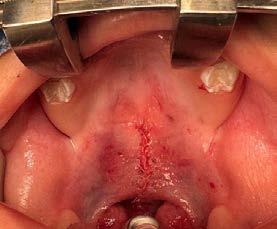

Por lo que se propone procedimiento quirúrgico con la evidente comunicación oroantral al realizar las extracciones de los órganos dentales involucrados. Previa asepsia y antisepsia, colocación de campos estériles, extracción de segundo y tercer molar superior derecho e incisión envolvente con descarga mesial (Figura 3), rotación y afronte mediante puntos simples de la bola adiposa de Bichat para el cierre de la comunicación oroantral (Figura 4), farmacoterapia con base en amoxicilina con ácido clavulánico. Una semana después refiere no presentar rinorrea y mejoría al 100% de la obstrucción. Posterior a 6 meses de evolución clínica (Figura 5) y radiográficamente (Figura 6), no se observa comunicación oroantral o paso de líquidos de la cavidad oral a la cavidad nasal.

4. Cierre de comunicación con la bola adiposa de Bichat.

Figura 3. Colgajo envolvente con liberatriz mesial y alveolo postextracción.

Figura

Figura 5. Fotografía oclusal de 6 meses de evolución.

6 meses posterior a la cirugía.